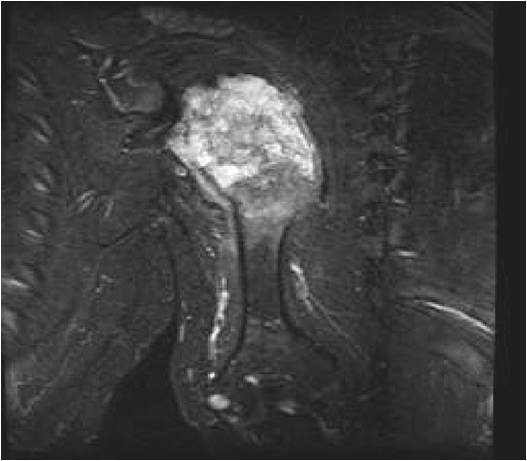

MRI:

- Lobulated margin (Lobular Growth Pattern)

- T2 Weighted Images: High Signal Intensity

- High water content shows as high signal on T2 weighted images

- Marked increased intensity long TR images

- There should never be any cortical destruction nor a soft tissue component. If this exists then the tumor must be a chondrosarcoma.

- Endosteal scalloping and cortical expansion is acceptable for phalangeal tumors. In most benign long bone cartilage tumors there is minimal endosteal scalloping but there should be no cortical expansion nor thickening. There should be no cortical destruction and no soft tissue component associated with an enchondroma. Cortical destruction, periosteal thickening, cortical expansion and a soft tissue component indicates a chondrosarcoma of the long bone.